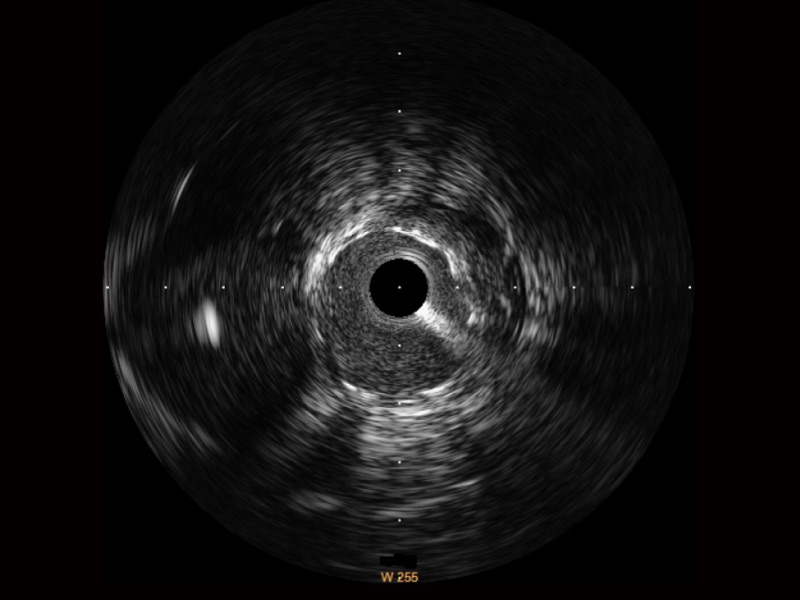

• 传统IVUS图像

对比传统IVUS导管成像,1xBET宽频IVUS图像的近场支架梁显影更细腻,远场中膜外血管仍清晰可辨,兼顾远中近,兼顾分辨力与穿透深度